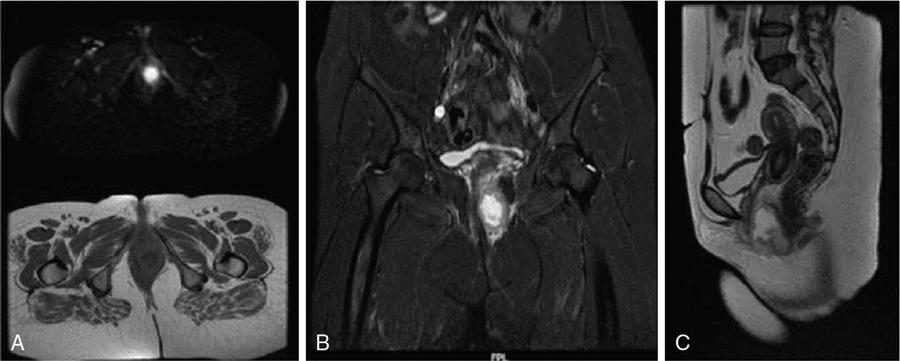

VAGINAL CYSTS Sumeena The vagina is a fibromuscular sheath. Vagina extends from uterus to the vulvar vestibule. The vagina is located in the middle compartment of the pelvis and it is related anteriorly to bladder and urethra, posteriorly to lower rectum and anal canal. The length of vagina ranges from 4 to 12 cm. The posterior wall of vagina is longer and it ends in posterior fornix; the anterior wall is shorter and ends in the anterior fornix. The wall of vagina is composed of three layers: (a) The mucosa consists of nonkeratinized stratified squamous epithelium without glands and its hormone sensitive layer; (b) the muscularis made up of connective tissues and smooth muscle; and (c) the adventitia, which is fascia that connects the vagina to the surrounding pelvic structures and maintains support. The prevalence of vaginal cysts is estimated to be less than 1%. They typically present in the age of 30–40s. Their origin may be Müllerian, Wolffian, squamous or urogenital. Risk factors for vaginal cysts: The vagina may be underevaluated due to probe positioning in routine pelvic US and due to poor vaginal tissue characterization in CT examinations. Though MR imaging provides good tissue characterization, we must focus on the vaginal region to identify any incidental findings. The strengths and limitations of each imaging modality must be understood in assessing the vagina. US is the first-line imaging modality since it is readily available, cost-effective, high resolution and no ionizing radiation. Limitations include operator dependence and patient obesity. The major limitation with transabdominal approach is that the upper portion of the vagina is seen well; the inferior aspect of the vagina is obscured due to shadowing from the pubic symphysis. Limitation with transvaginal US is that the transducer is typically placed in the anterior or posterior fornix which bypasses the perineum and vagina. US imaging needs methodic evaluation performed from introitus to the fornices and include transabdominal, transvaginal and translabial approaches. Due to the poor vaginal tissue characterization and ionizing radiation, CT is usually not indicated for evaluation of the female pelvis. When US is inconclusive, pelvic MR imaging is recommended. The vaginal wall anatomy is best imaged with T2-weighted sequences. The vaginal mucosa has high signal intensity, circular and longitudinal muscle layers have intermediate signal intensity. Embryonic Traumatic Epithelial inclusion cyst/epidermal inclusion cyst/squamous inclusion cyst Skene’s duct cysts Urethral diverticulum Infective Filariasis Vaginitis emphysematosa Epidermoid cyst Sebeceous cyst Endometriotic cyst Ciliated cyst Paraurethral mass Rare Lymphangioma Postradiation Haematocolpos Rectocele and cystocele Prolapsed ectopic ureterocele Large nabothian cyst, tunnel cluster cysts Adenoma malignum Most common type of vaginal cysts, almost up to 40% of cystic masses. As Müllerian epithelial tissue can present anywhere in the vaginal wall, the cysts can also be found anywhere within the vaginal walls. Most common location is along the anterolateral aspect of the vagina. Müllerian cysts present as small, midline cystic masses, with no symptoms and require no treatment. Symptomatic vaginal cysts are treated by excision. The entire cyst wall must be removed to prevent recurrence. Adenocarcinoma can arise in a Müllerian vaginal cyst. The epithelium of Gartner’s cysts is devoid of cytoplasmic mucicarmine and PAS-positive material, in contrast to the epithelium of Müllerian cysts. MRI – Gold standard. Mucus secretion is a unique feature of Müllerian cysts and shows heterogeneous T2 signal. Extent of the cyst, surrounding structures are better evaluated in MRI prior to surgery. Incomplete regression of Wolffian ducts leads to the development of Gartner duct cysts. They are usually noted in the upper anterolateral wall of the vagina above the inferior border of the pubic symphysis. Typically less than 2 cm. When these cysts are large enough, they can compress the urethra causing urinary symptoms. It can also be associated with abnormalities of the metanephric urinary system such as an ectopic ureter, unilateral renal agenesis and renal hypoplasia. USG: Anechoic structure in the upper vagina; transvaginal US provides better differentiation than the transabdominal approach. Fig. 11.19.1.1; T2-axial image shows hyperintense cystic lesions, one in posterior fornix and another one in anterior aspect of upper vagina. Both the lesions are above the level of pubic symphysis. Fig. 11.19.1.2; T2-sagittal image shows hyperintense cystic lesions, one in posterior fornix and another one in anterior aspect of upper vagina. Both the lesions are above the level of pubic symphysis. Bartholin glands are commonly located posterolateral to the vaginal introitus and medial to the labia minora. The obstruction of the gland’s duct either by a stone or a stenosis, which may be caused by prior infection or trauma, leads to Bartholin gland cysts. Cysts are typically round and unilocular, seen at or below the level of the pubic symphysis, usually asymptomatic. This is most apparent on coronal plane imaging. USG: Bartholin gland cysts can be imaged by a transperineal approach. Although these cysts are usually asymptomatic, occasional infection may necessitate drainage of the cysts (Fig. 11.19.1.3). Bartholin gland duct can be obstructed due to stone or stenosis, later which can become infected. The Bartholin’s gland abscess size ranges from 2 to 8 cm with an average of 3 to 4 cm. Antibiotics with or without surgical drainage is the treatment. Marsupialization may be needed in recurrent conditions. USG-complex cystic hypoechoic to anechoic lesions increased throughout transmission. Colour Doppler may show peripheral hyperaemia. Spectral flow – low resistance arterial flow. MRI-T2: Tends to show heterogeneous signal T1 C+ (Gd): pericystic enhancement may be seen (Fig. 11.19.1.4). Vaginal inclusion cysts – also known as epidermal inclusion cysts, most commonly are seen in the distal posterior or lateral vaginal wall at sites of previous trauma or surgery. Inclusion cysts are lined by a stratified squamous epithelium and contain keratinous material. Symptomatic cyst needs treatment. The treatment of choice for symptomatic cysts is marsupialization. MRI-DWI shows restriction (Fig. 11.19.1.5). Skene glands are paired structures in periurethral location near external urethral meatus with ducts draining into the urethra. Skene gland cysts can cause UTI or urethral obstruction. They are distinguished from urethral diverticulum, which are usually midurethral. In T2-weighted images, Skene duct cysts seen as round or oval hyperintense lesions just lateral to the external urethral meatus. MRI:T1 hyperintense due to proteinaceous material. T2 hyperintense. Fluid–fluid level if complicated with debris or haemorrhage (Fig. 11.19.1.6). It may be congenital or result from infection or obstruction. In females, diverticula commonly extends from the posterolateral wall of the mid-portion of the urethra. During voiding cystourethrography (VCUG), they are seen best on postvoid images. Transrectal US shows a cystic mass in proximity to the urethra and it will be seen anterior to the vagina. Lack of radiation and capacity to differentiate solid from cystic masses is the advantage of US over CT. CT shows a periurethral lesion with low attenuation. MRI shows T1 hypointense and T2 hyperintense fluid signal intensity. Postcontrast imaging with gadolinium is used to evaluate infection or inflammation. Adenoma malignum of the cervix is a rare variant of cervical mucinous adenocarcinoma. VAGINAL MALIGNANCIES Rupa Renganathan, Suchana Kushvaha The primary vaginal carcinoma is a very rare gynaecological malignancy and accounts for 2%–3% of genital tract malignancies and 10% of all vaginal malignancies. It is defined as a cancer found in the vagina without histological or clinical evidence of cervical or vulvar malignancy and without previous history of treatment of cancers in the last five years. The commonest primary carcinoma is squamous carcinoma, and other rare primaries are adenocarcinoma, melanoma and sarcomas. The secondaries in the vagina are much more common than the primary and account for more than 80% of vaginal malignancies. Primary vaginal carcinoma is common in elderly, however, seen in the younger women when associated with human papillomavirus (HPV 16 and 18). Vaginal carcinomas are staged based on FIGO classification. Management of the cancer is usually based on the stage of the disease and the histological subtypes. Vagina is an elongated fibromuscular structure connecting the uterus with the vulva. It is approximately 7–9 cm long. The long axis is oriented 90 degrees to the uterine axis and its upper part is oriented almost horizontally and in plane with the pelvic floor. It is lined by the nonkeratinizing stratified squamous epithelium. It has anterior, posterior and lateral walls. The upper portion of vagina is invaginated by the cervix such that a space is created between its walls and the cervix called fornices. The posterior fornix is deeper than the anterior fornix. Anterior wall is separated from the bladder base and the urethra by the anterior vesicovaginal septum while the posterior wall is separated from the rectum by rectovaginal septum. The posterior fornix is covered with the peritoneal reflection that forms the Pouch of Douglas. It is supplied by the vaginal arteries, originating from the internal iliac artery and branches of uterine, middle rectal and inferior vesical arteries. There is considerable overlap in the lymphatics between the various parts of vagina. The upper two-thirds of the vagina drain into the pelvic lymph nodes that include external, internal and common iliac groups and the lower third into the superficial inguinal and femoral lymph nodes. The posterior vaginal wall also drains into the perirectal lymph nodes. MRI is the standard imaging modality for local staging of cancers and also for assessment of treatment response and surveillance due to superior soft tissue resolution, multiplanar capability. In a relaxed state, it is seen as a ‘H’ shaped structure posterior to urethra with the anterior and posterior walls being opposed to each other. The vaginal lumen may have secretions or blood-causing distention of its lumen. The anatomy of the vagina is best depicted on T2w images where three layers of its wall can be distinguished in a nondistended state. The mucosa is T2 hyperintense with a hypointense submucosal and muscularis layer beneath it. It is surrounded by adventitia which is hyperintense due to the venous plexus (Fig. 11.19.2.1A and B). For accurate staging purposes, vagina should be distended with ultrasound gel with the help of a syringe and infant feeding tube (Fig. 11.19.2.1C and D). Before inserting gel, patient consent must be taken and her marital status should be enquired. Care must be taken that air is not insufflated while introducing the jelly. Jelly can also be introduced in patients other than carcinoma vagina in cases where vaginal involvement is suspected in other malignancies. After adequate distention, the walls get separated and the fornices are better delineated. For staging purposes, the vagina is divided into three parts. The upper one-third lies above the level of the bladder base and includes the fornices. The middle one-third is opposite to the bladder base and the lower one-third opposite to the urethra (Fig. 11.19.2.1D). Ultrasound owing to its limited field of view and inaccurate staging is not used for imaging of vaginal pathologies. CT has poor contrast resolution and is used only for lymph nodes staging in known patients of vaginal malignancy. PET CT has the advantage in that it combines both the functional and anatomical information about the tumour. While performing PET for the gynaecological malignancies, general measures to reduce bladder activity, like Foley’s catheterization, IV hydration and diuretic administration, are adapted and the image acquisition is done from the pelvis cranially. The advantage of PET beyond providing functional information is that it provides information about distant metastases. The presence of nodal metastases in patients with vaginal cancers portends a poor prognosis and alters the management. In a study by Christensen et al., PET CT was found to be more sensitive and carried greater negative predictive value as compared to MRI for detection of lymph nodes. However, commonly seen inflammatory and the reactive lymph nodes may show uptake. Node biopsy or excision is mandatory wherever the metastatic involvement is indeterminate or questionable. PET CT is recommended for restaging the recurrent tumour, and differentiating the treatment changes from recurrence in vaginal carcinomas. In cases of vaginal sarcomas, it is used for grading, staging and follow-up imaging. MRI is the main investigation for evaluation of vaginal masses and for both staging and surveillance. Patients are requested to be fasting for at least 4 hours to limit bowel motility and to empty the bladder 1 hour before the study to achieve moderate distention of the bladder. Use of antispasmodic agents like Butylscopolamine 40 mg IM/IV or Glucagon 0.5–1 mg IV/IM can also be considered to reduce bowel movements. The vagina should be distended with about 60 mL of Ultrasound Gel for evaluation of vaginal lesions. The patient is imaged in supine position with phased array abdomino pelvic coil. The saturation band is usually placed anterior and superior to the field of view. T2 imaging remains the mainstay for evaluation of vaginal tumours. The basic sequences for evaluation of vagina lesions are T2 sagittal, axial, coronal and oblique axial, T1 axial and diffusion-weighted imaging in axial plane. The high-resolution oblique axial along the plane of vagina is the best sequence which demonstrates the tumour and its extent. The study may be completed by contrast injection. The sequences for contrast evaluation will include pre-T1 with fat saturation, followed by dynamic contrast injection and postcontrast T1 fat saturated acquisition. The most common clinical presentation would be painless vaginal bleeding (65%–80%) followed by vaginal discharge, pelvic pain, urinary symptoms and mass being felt in the vagina. The primary carcinoma are usually squamous cell carcinoma and accounts for about 80% of cases. They are more commonly seen in the upper third in the posterior wall. It is associated with HPV and about 30% of women also have history or associated intraepithelial and invasive cancers of cervix and vulva. About a third of patients present with lymph nodal metastasis in the pelvis or inguinal region at the time of clinical presentation. Adenocarcinoma accounts for only 9% of primary vaginal malignancies, and they are usually seen in the anterior wall of the upper third of the vagina. They affect younger age group (14–21 years) and arise from the lesions such as endometrial deposits and the vaginal adenosis. About two-thirds of the cases have exposure to Diethylstilbestrol to their mothers. When seen in older women, they are usually clear cell carcinomas. Staging of vaginal carcinoma with MRI parallels clinical FIGO staging (Figs 11.19.2.2–11.19.2.4). The tumour is best seen on T2-weighted sequences where it is seen as an intermediate signal (higher than muscle and lower than fat). Adenocarcinomas typically exhibit high T2 signal. Because of the signal on T2, the tumour is well delineated from the vaginal wall which displays low signal intensity. When the tumour is limited to vagina, it is difficult to be seen on T1 sequences unless it causes a contour abnormality as the tumour will be isointense on T1. Stage I tumours are those which are either seen as mass/plaque like thickening but will be limited to vagina and will be diagnosed if the hypointense T2 signal of the vaginal wall is preserved (Fig. 11.19.2.5). When the tumour disrupts this hypointense layer and extends into the paravaginal fat, the staging becomes Stage II (Fig. 11.19.2.6). The loss of normal signal of the vaginal wall should be looked at all three orthogonal planes to identify subtle loss of the signal which is the important finding which upstages the tumour.